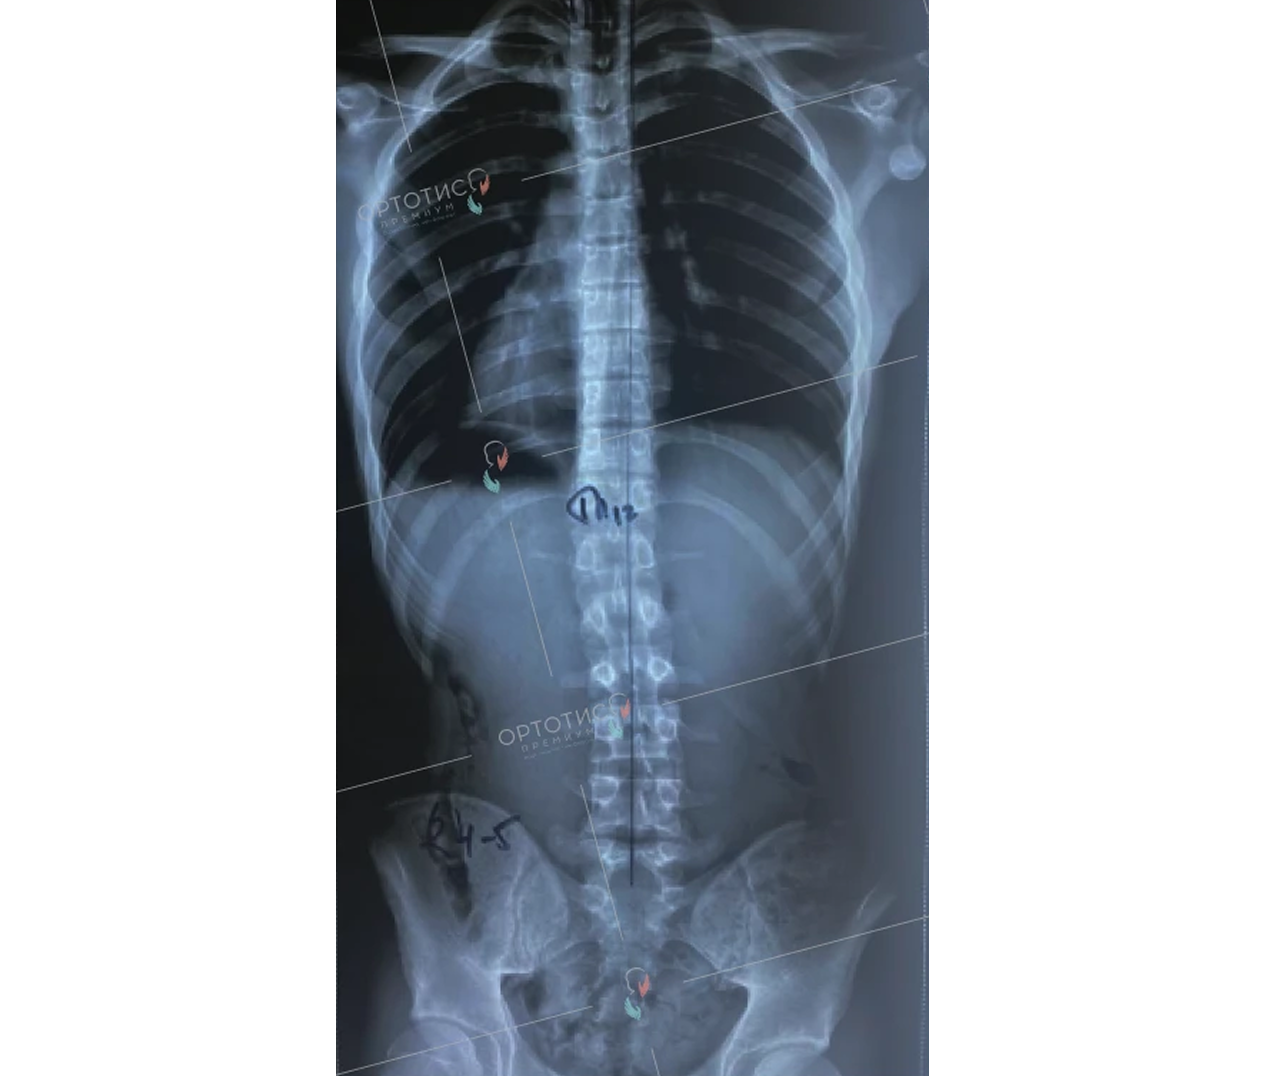

Корсет Шено — это «золотой стандарт» в лечении сколиоза у детей и подростков. В клинике Ортотис Центральная Азия в Алматы мы изготавливаем активные ортопедические корсеты, которые не просто удерживают позвоночник, а эффективно исправляют деформацию.

• Идиопатический сколиоз с углом искривления от 20° по Коббу;

Мы используем высокоточное 3D-моделирование, что позволяет создать корсет, идеально соответствующий анатомии ребенка. Это обеспечивает максимальную коррекцию при сохранении мобильности. Наши техники-ортопеды в Алматы проводят регулярную коррекцию изделия по мере исправления позвоночника.